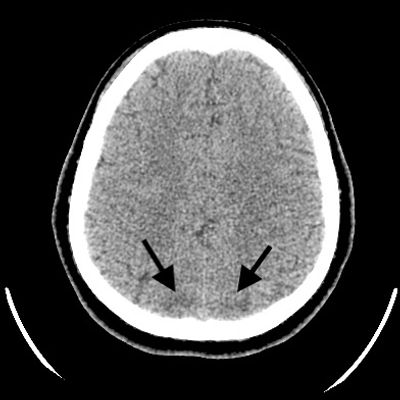

On day 1 post-extubation, she again saw the black figure pacing around in the ward for two hours continuously before it abruptly vanished. She panicked and attempted to abscond from the ward. There were no other psychotic symptoms, headache or blurred vision. Social interaction and cognitive functions were intact. The orientation and consciousness level were good. The blood pressure was normotensive 136/84mHg with oral labetalol 200mg ter die sumendum. There was haemolytic anaemia indicated by lowering of haemoglobin from 10.7 g/dL on admission to 8.16 g/dL in the absence of bleeding. The liver enzymes were raised and the platelet lowered but both normalized within a week of postpartum. Urine protein was positive. These results were suggestive of HELLP (Hemolysis, Elevated Liver Enzymes, and Low Platelet Count) Syndrome associated with the eclampsia. Brain CT scan revealed hypodense areas at bilateral posterior parts of occipital lobe suggestive of PRES. Brain MRI was not proceed due to unavailability at the district hospital.

Since PRES is a clinico-radiological diagnosis, the radio imaging of the brain is essential to confirm the diagnosis. In this patient, the CT brain showed hypodense areas at bilateral posterior parts of the occipital lobe which is the typically affected area in PRES accounting for 22% of all cases. The posterior occipital lobe is the watershed area of the posterior cerebral artery. Thus, it is vulnerable to cerebral hypoperfusion (3). The putative pathophysiology is that a sudden rise in blood pressure triggers severe vasoconstriction leading to cerebral hypoperfusion due to the reduction of the cerebral blood flow. The cerebral hypoperfusion activates the release of endothelial agonist, vasodilators, catecholamines, vasopressin, thromboxane and endothelin I. These substances trigger the renin-angiotensin-aldosterone system and result in the release of pro-inflammatory cytokines which are directly cytotoxic to the vessel wall. The damage impairs the blood-brain barrier function and causes cerebral vasogenic edema (3).

Figure 1: Brain CT scan showed hypodense area at posterior parts of the bilateral occipital lobes